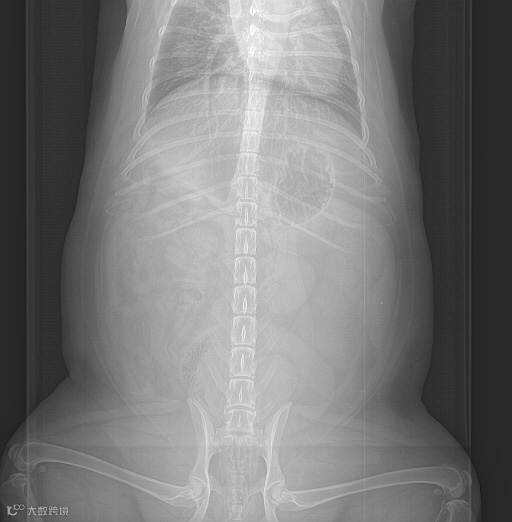

是确保诊断区域图像质量的关键因素。标准的摆位减少断层图像的变形,利于直接诊断,同时减少非诊断区域对诊断区域的干扰和导致的部分伪影。

双后肢未拉直

影响髋部观察

是确保图像覆盖所需解剖区域的关键。评估时应检查图像是否覆盖扫描区域,所需解剖结构是否完整显示,没有被截断或超出范围的情况。